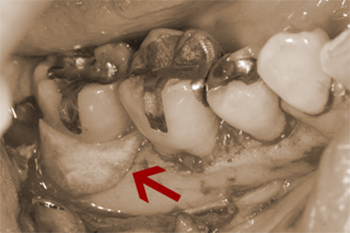

右下奥歯が腫れると来院。最奥歯の周囲の骨が狭くやや深くなくなっています。

術前のレントゲンでも歯の周囲の骨が不整であることが理解できます。

カラー写真だと一見したところ異常が無い様に思えますが、、、

※血が苦手な方に配慮して画像の色味を修正しています。

歯肉を切開し骨をあらわにしたところ、最奥歯の骨の欠損が確認できます。

AFTER ( 術中・術後 )

欠損部にエムドゲイン、周囲から採取した骨を填塞し、その上に膜(バリアメンブレン)を設置しています。

この方の場合は手前の歯のすり減り等を考慮すると歯ぎしりなどの噛む力のコントロールがなされていない、または噛み合わせが悪く現状に至ったと推察しました。

基本治療から3ヵ月しても改善が見られなかったため再生療法を施術し現在も加療中です。